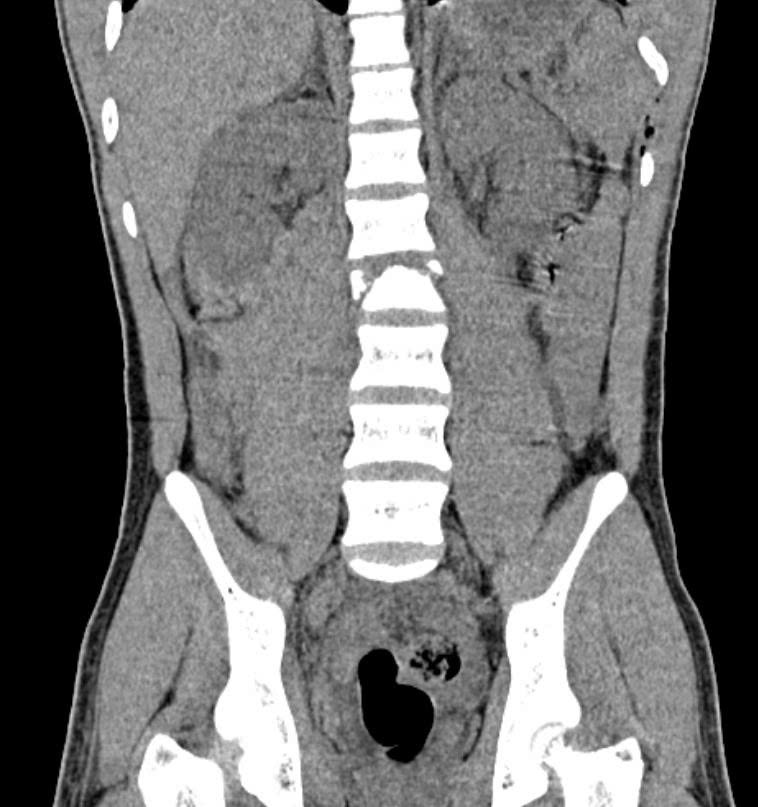

Hình ảnh chụp cắt lớp cho thấy bệnh nhi bị gãy xẹp đốt sống L2 (Ảnh: Bệnh viện cung cấp)

Tại một bệnh viện địa phương, các kết quả chẩn đoán hình ảnh cho thấy em bị gãy xương sống, tủy bị đứt, xương sống gãy vỡ phức tạp, nên được chuyển khẩn vào Bệnh viện Nhi đồng 2. Ê-kíp phẫu thuật đã nhanh chóng đặt dụng cụ cố định cột sống, giúp em giảm đau và tránh lở loét do nằm lâu.